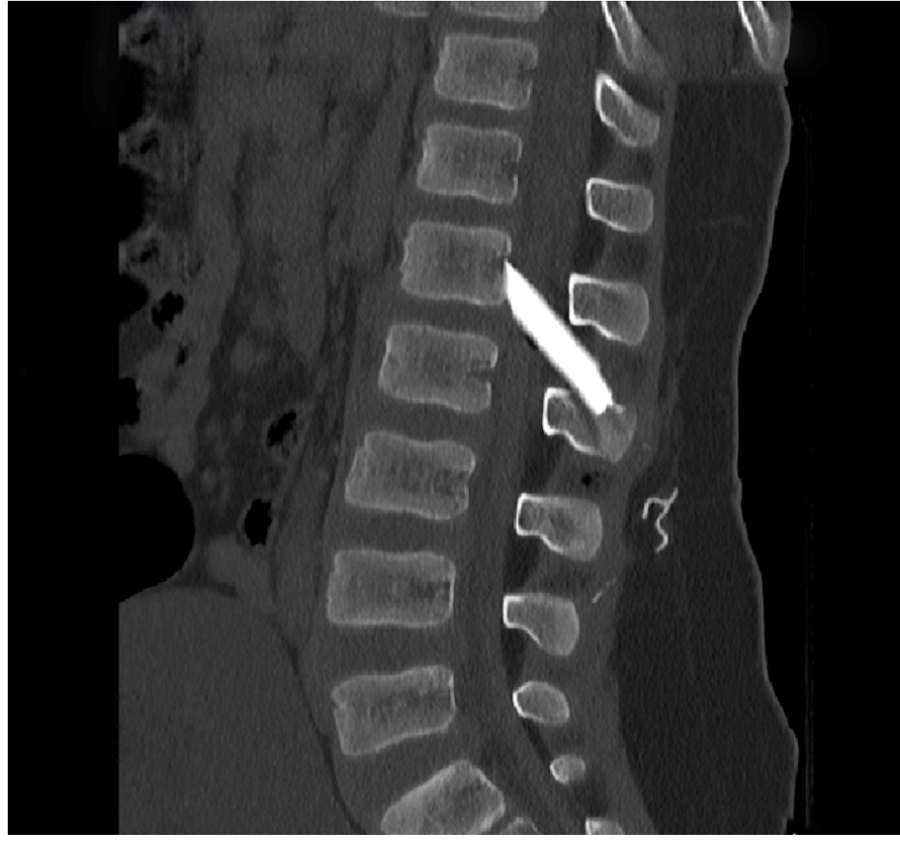

Οι μαγνητικές και αξονικές τομογραφίες πραγματοποιήθηκαν άμεσα, επιβεβαιώνοντας τις αρχικές υποψίες: δύο μεγάλα κομμάτια γυαλιού είχαν ενσφηνωθεί στη σπονδυλική στήλη, εισχωρώντας εντός του σπονδυλικού σωλήνα σχίζοντας την ιππουρίδα και την μήνιγγα που την περιβάλλει.

Ακολούθησε άμεση εισαγωγή του παιδιού στο χειρουργείο, όπου με πολύ προσεκτικούς χειρισμούς και τη χρήση προηγμένου εξοπλισμού, όπως το σύστημα χειρουργικής πλοήγησης, πραγματοποιήθηκε επιτυχής αφαίρεση όλων των

κομματιών γυαλιού μετά από ένα πολύωρο και απαιτητικό χειρουργείο.